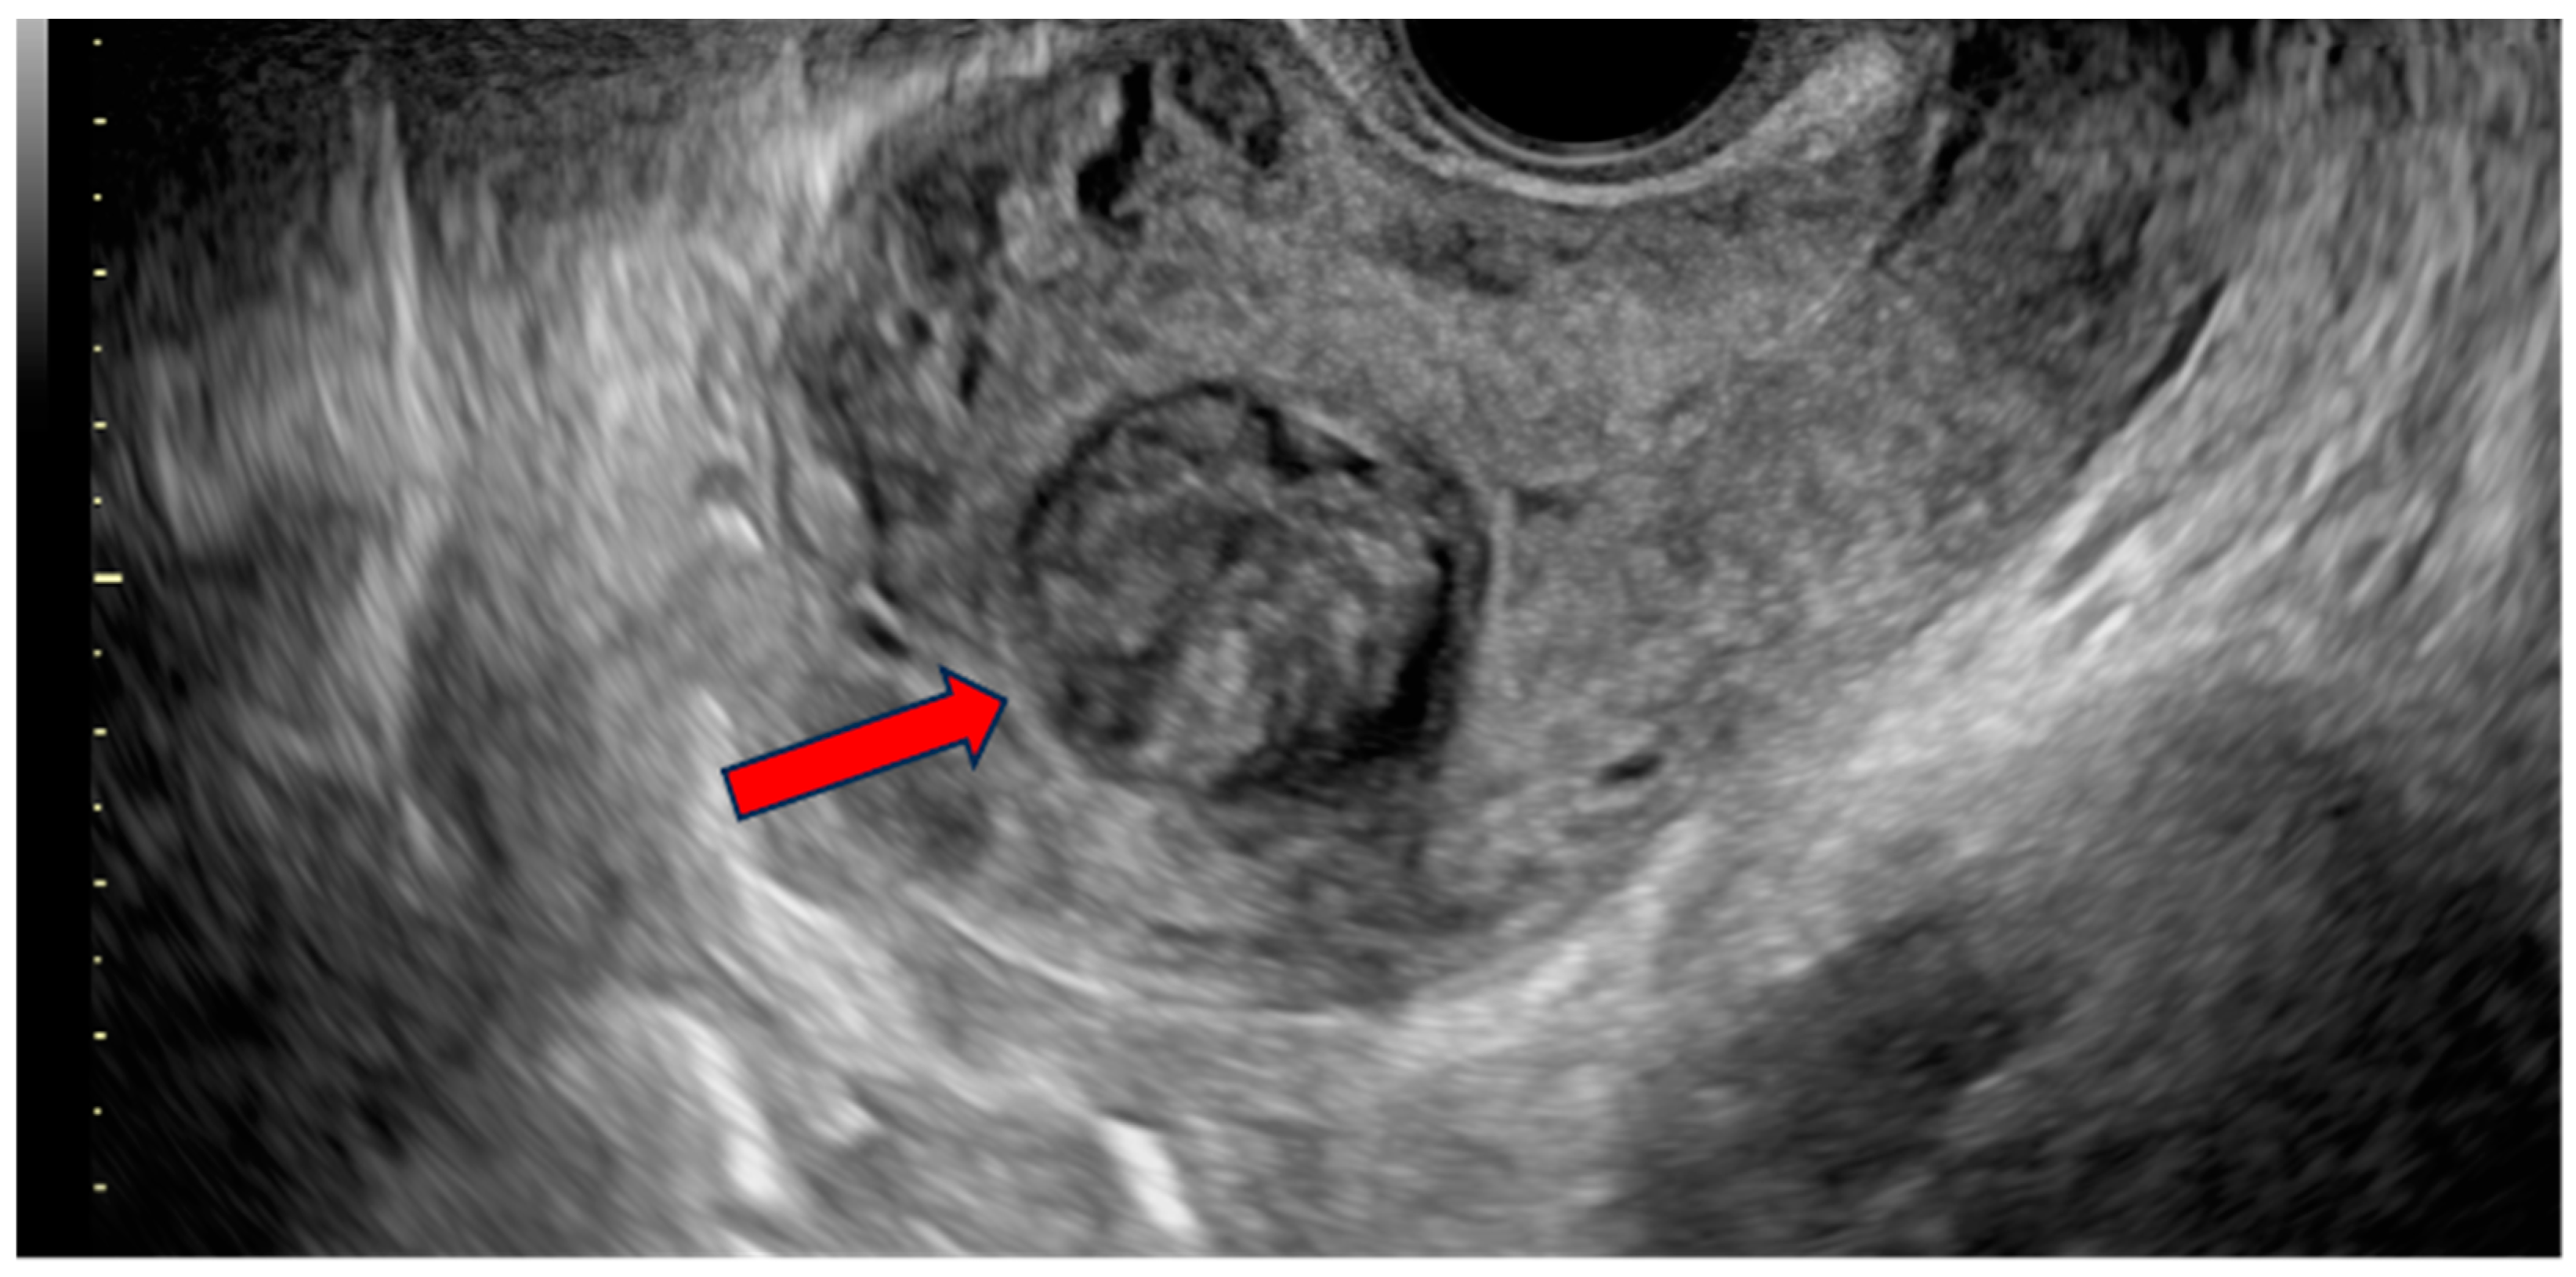

On examination, there were not any palpable masses in the abdomen. The uterine corpus was not enlarged, not painful, and mobile. The cervix was normal-looking, although there was some bloody discharge and blood clots in the vagina. The adnexa were not palpable per vaginal examination. A two-dimensional/three-dimensional transvaginal ultrasound (2D/3D-TVS) examination using a Voluson E10 (GE Healthcare Ultrasound, Milwaukee, WI, USA) revealed a single oval-shaped submucosal lesion located within the uterine fundus, protruding into the uterine cavity (Figure 1 and Figure 2). The lesion measured 32.2 × 29.4 mm and had mixed echogenicity and well-defined borders without acoustic shadow. No calcifications or cystic areas were visible in the lesion. The uterus was anteverted, measuring 64 × 68.9 mm, with a thin endometrium and signs of adenomyosis within the myometrium. The adnexa was normal bilaterally, and there was no fluid in the Douglas pouch. The examination was performed by level three experts according to the European Federation of Societies for Ultrasound in Medicine and Biology (EFSUMB, www.efsumb.org, accessed on 20 October 2024).

Figure 1.

Transvaginal ultrasound (TVS) image showing a sagittal view of the patient’s uterus. A well-defined, solid lesion (red arrow) of mixed echogenicity is visualized within the borders of the uterine cavity. No evident acoustic shadow is present. The myometrium surrounding the lesion displays visible heteroechogenity with rich vascularization.

There are no ultrasound features that could specifically indicate malignancy in uterine smooth-muscle tumors [11]. Distinguishing STUMP from leiomyosarcoma based on imaging methods is virtually impossible. However, due to the widespread availability of ultrasound, these lesions are often visualized and described using this method. The most common morphological ultrasound features indicating the risk of malignancy are irregular borders of the lesion, irregular cystic areas, non-uniform echostructure, mixed echogenicity, and rich vascularization [21]. Malignant lesions are more commonly single, bigger than benign, and exhibit rapid growth.

On the contrary, visualization of normal myometrium and acoustic shadow is more typical for benign lesions [21]. The presence of calcifications is not indicative of the malignancy of the lesion; however, some authors suggest they are more common in benign leiomyomas [22]. In general, ultrasonography is not a perfect method to differentiate benign and malignant lesions with moderate specificity and sensitivity [23]. However, the use of these ultrasound features in combination with clinical data, such as age and presence of symptoms, in the form of diagnostic algorithms can be effective as a sensitive method of selecting patients at risk for STUMP or sarcoma with high negative predictive value, but at the cost of significantly lower specificity [21]. It is particularly challenging to differentiate sarcomas and STUMPs from degenerating leiomyomas with heterogeneous echogenicity and central necrosis. In our case, the ultrasonographic appearance was not characteristic of malignant lesions, although the lack of acoustic shadowing, mixed echogenicity of the lesion and rich vascularization are more frequently seen in STUMPs and leiomyosarcomas [21].